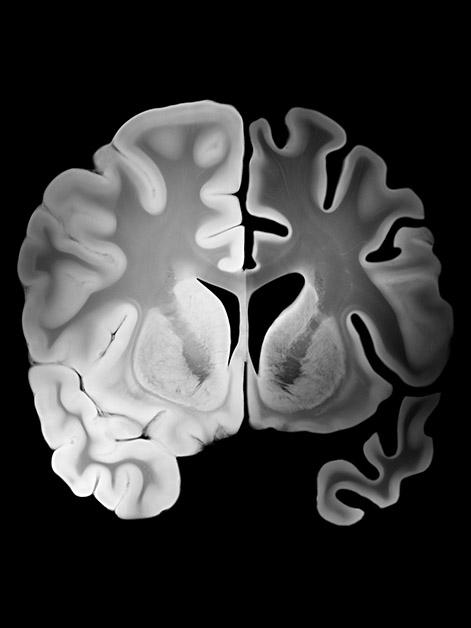

אוכלוסיית העולם מזדקנת, ומחלות מוח ניווניות ובפרט אלצהיימר הן בעיה בריאותית הולכת ומחריפה. היעילות של הטיפולים הקיימים, כולל טיפולים חדשים שאושרו לאחרונה, עדיין אינה מוכחת דיה, וקיים צורך דחוף בטיפולים חדשים. אחד מסימני ההיכר המרכזיים של אלצהיימר הוא הצטברות של משקעי החלבון עמילואיד-בטא במוח וכן סמני דלקת ברקמת המוח. צוות המחקר בראשות פרופ' עידו עמית מהמחלקה לאימונולוגיה מערכתית במכון ויצמן ופרופ’ יהונתן קיפניס מבית-הספר לרפואה של אוניברסיטת וושינגטון בסנט לואיס, ובהובלת הפוסט-דוקטורנט ד"ר פבל בוסקוביץ, הוציאו תאי T של המערכת החיסונית מעכבר בריא והנדסו אותם גנטית כך שיזהו ויגיבו לחלבוני עמילואיד במוח. החוקרים הזריקו את התאים המהונדסים לעכברים שבמוחותיהם כבר היו משקעי עמילואיד-בטא המאפיינים אלצהיימר. ההזרקות הובילו לירידה משמעותית במשקעים וכן לירידה בסמני דלקת של רקמת המוח.